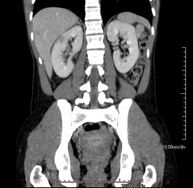

Prova diagnòstica que consisteix en obtenir imatges bi i tridimensionals del ronyó i del sistema urinari d'alta definició anatòmica mitjançant l'ús d'un equip de TC (Tomografia Computeritzada). Es realitza l'estudi abans i després de l'ús de contrast iodat en diferents "fases renals" per a una valoració funcional i anatòmica: parènquima renal, urèters, bufeta urinària, artèries i venes renals, etc. així com les estructures adjacents (vena cava inferior, aorta abdominal, fetge, melsa, etc.). Està especialment indicat quan hi ha sospita de lesions renals, en pacients amb sang a l'orina o hematúria, etc. - TC Urològic